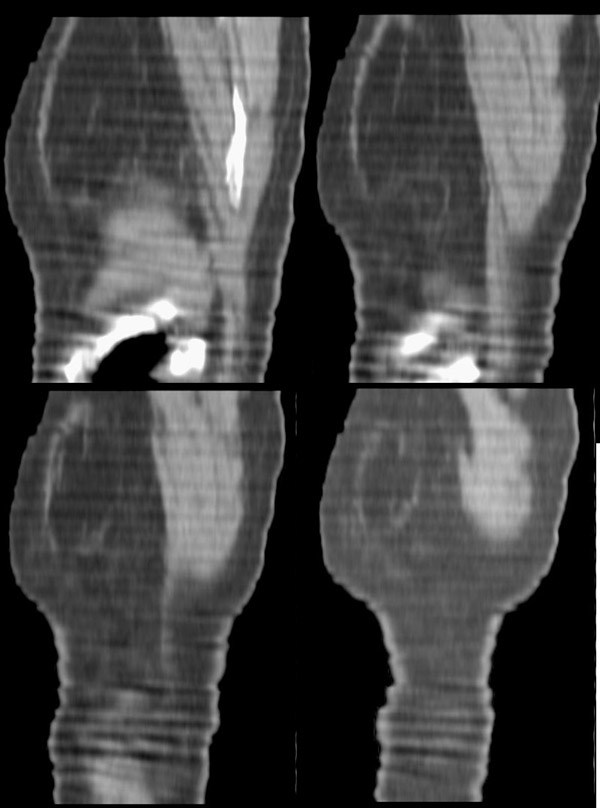

以下是引用形影不离在2008-5-19 21:13:00的发言:[br]左侧胸壁脂肪瘤;肺部还是考虑心衰并肺水肿,胸腔积液。

以下是引用panyishengct在2008-5-19 21:48:00的发言:[br]左侧胸壁脂肪瘤;肺部还是考虑肺水肿,胸腔积液。 [br] [br]左肺门见一团状影,纵隔见淋巴结,建议治疗后复查,以排外中央型肺癌